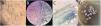

Trichoscopic imaging were obtained from all the patients from the series (Fig. 1A), as well as direct KOH examinations and mycological cultures (Fig. 1B-D). The clinical signs reported included erythematous-scaly lesions in the occipital and/or temporal regions clinically very similar to psoriasis or seborrheic dermatitis, which is why they had previously been treated in other centers with topical corticosteroids in some cases, resulting in worsened lesions (Fig. 2A; also see one of the most striking cases of the series included in panel B-Figure 2 of the references number 6).6 Connubial TC in infected patients from hair salons was also a common finding. Less frequently, patients with black dot TC (Fig. 2B) and inflammatory TC (Fig. 2C) were seen. It was not uncommon that many of these patients (especially those with black dot TC) were asymptomatic carriers, being trichoscopy of great help in their detection.7 Similarly, isolated cases of patients simulating alopecia areata and cradle cap in the youngest female patient of the series were also found (Fig. 2D), whose father, with TC diagnosed in the clinic and acquired at a hair salon, had infected her. All cases were reported to the Provincial Health Delegation of Malaga, Spain (presentation summarized in Fig. 2E) to locate the centers where the infections had occurred to stop the infections from spreading somewhere else.